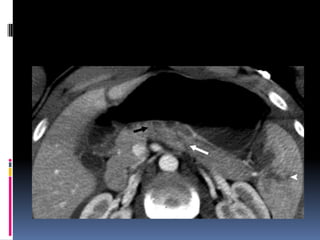

INJURIA HEPÁTICA Grados de severidad RadioGraphics 2009; 29:2033–2053